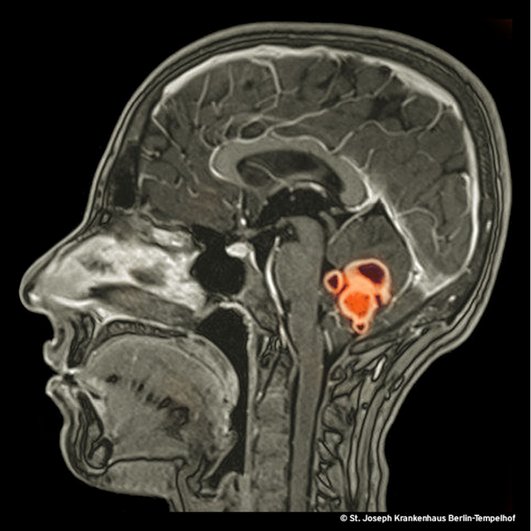

Das Bild zeigt eine Kernspinntomografie des Kopfes einer an sich immungesunden jungen Frau ohne HIV-Infektion mit Tuberkulomen im Kleinhirn. Sieben Jahre zuvor wurde sie in ihrem Heimatland Rumänien wegen einer tuberkulösen Perikarditis behandelt. Sie muss damals bereits eine unentdeckte Mitbeteiligung des zentralen Nervensystems gehabt haben. S I E B E N Jahre nach dem Tod der Tuberkelbazillen, befreit sich das Immunsystem aus der Manipulation durch die Erreger und reitet eine Attacke gegen Bestandteile avitaler Bakterien, die im Hirngewebe überdauert haben. Die Tuberkulome sind der sichtbare Ausdruck dieser Schlacht. Woher nehmen wir die Sicherheit, dass die Bakterien tot sind: Die Patientin hatte zeitgleich mit neurologischen Symptomen multiple einschmelzende Lymphknotenschwellungen entwickelt. Zahlreiche aus den Lymphknoten entnommene Gewebeproben waren PCR-positiv, aber nicht ein einziges Mal konnte M. tuberculosis angezüchtet werden. Auch wenn ein Restzweifel bleibt, sind wir uns wegen der negativen Kulturergebnisse ziemlich sicher, dass die Patientin nicht an einem mikrobiologischen Rezidiv, sondern an einem immunologischen Phänomen erkrankt war. Dieses Phänomen bezeichnet man als Paradoxical Upgrading Reaction (PUR) oder Immunrekonstitutionsphänomen. Es tritt bei 2,4 bis 56 % der HIV-negativen Patient:innen mit Tuberkulose auf [2-6]. Die lange Zeitspanne zwischen der Ersterkrankung und dem Einsetzen der PUR macht diesen Fall besonders.

Die Herausforderung besteht darin, zwischen einem Rezidiv der Tuberkulose und den Folgen der wiedererwachenden Immunantwort zu unterscheiden. Die Gretchenfrage lautet: Sind die Bakterien die wir mikroskopisch oder molekularbiologisch finden tot oder lebendig? Da es auf diese Frage keine sichere Antwort gibt wählen wir in dieser klinischen Situation meist einen Kompromiss aus einer antituberkulösen und einer immunsuppressiven Therapie mit Prednisolon.